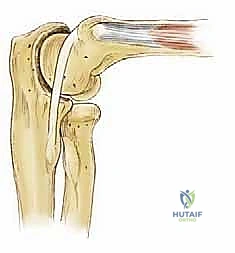

هو المفصل الأساسي المسؤول عن حركتي الثني (Flexion) والمد (Extension). يتكون من تمفصل البكرة العضدية مع الثلمة البكرية لعظمة الزند. يمر محور دورانه الثابت عبر اللقيمة الوحشية وأمام وأسفل اللقيمة الإنسية مباشرة. هذا التصميم الهندسي يوفر استقراراً جوهرياً عالي الكفاءة، مما يمنع الحركات الجانبية المفرطة. - المفصل الكعبري الزندي القريب (Proximal Radioulnar Joint):

هنا يكمن بيت القصيد في موضوعنا. في هذا المفصل، يتصل الرأس الصغير (Capitellum) المستدير والمحدب للعظم العضدي البعيد مع الرأس الكعبري (Radial Head) المقعر. هذا المفصل يتحمل العبء الأكبر من قوى الضغط المحوري. عادةً ما يظهر المفصل الزندي العضدي بزاوية وحشية (Valgus Angle) تتراوح بين 11 و16 درجة. هذه الزاوية الطبيعية تؤدي إلى تركز قوى الضغط تحديداً في الجانب الوحشي (الخارجي) للمرفق أثناء الأنشطة الرياضية أو حمل الأشياء الثقيلة. هذا الضغط المتكرر والعنيف هو العامل الميكانيكي الرئيسي في نشأة التهاب العظم والغضروف السالخ (OCD).